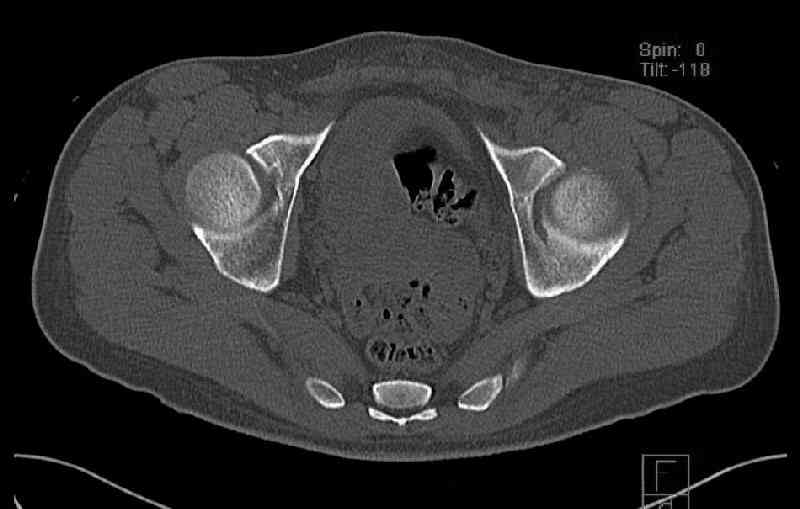

The last two images from the 3-D CT scan certainly makes the fracture look worse than the plan radiographs.

Some more images. Does it help to guess which part of the acetabulum is displaced?

Normal appearing SI joints and a healed posterior column limb... my bet's on caudal segment displacement.